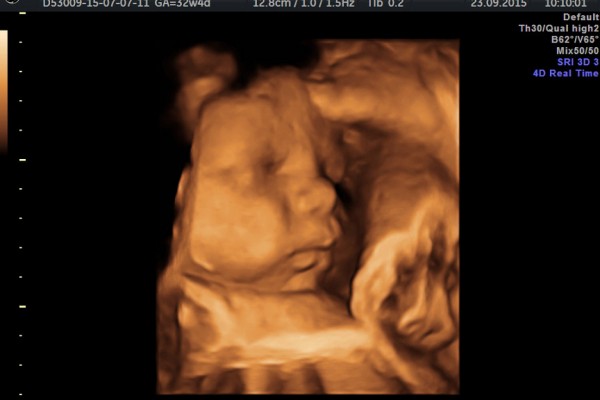

Prenatalna dijagnostika (dijagnostika tokom trudnoće) podrazumjeva različite dijagnostičke procedure koji se primjenjuju od početka trudnoće do poroda. Cilj ovog medicinskog principa rano otkrivanje potpune medicinske istine o nerođenom djetetu, o njegovoj građi i motorici, poremećajima građe ili funkcije organa ili sistema, nasljednim oboljenjima, rizicima od pobačaja, ranijeg rađanja, rađanja djeteta manje porođajne težine i sl. Prenatalna dijagnostika će omogućiti ne samo rano otkrivanje oboljenja fetusa već i njegovo liječenje “fetus kao pacijent“.

- 3D/4D ultrazvučni pregled ploda, tzv. anatomy scan